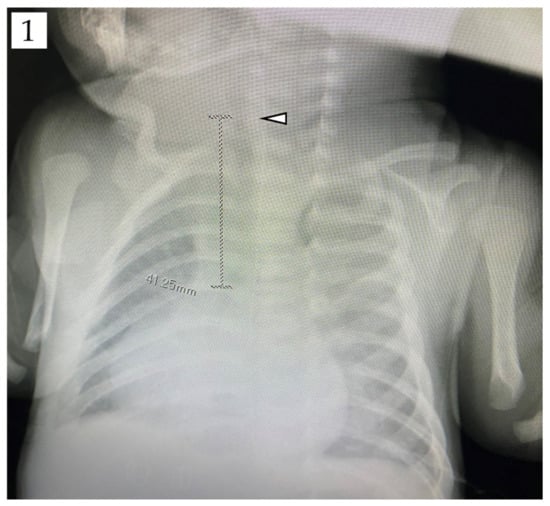

3.1. Parameters Showing the Strongest Correlation with Tracheal Length in Cardiac Pediatric Patients (Germany)

3.2. Validity of Tracheal Length Measurements in the Supine Position (Germany)

3.3. Association between Tracheal Length and Body Height in Cardiac Pediatric Patients in Germany